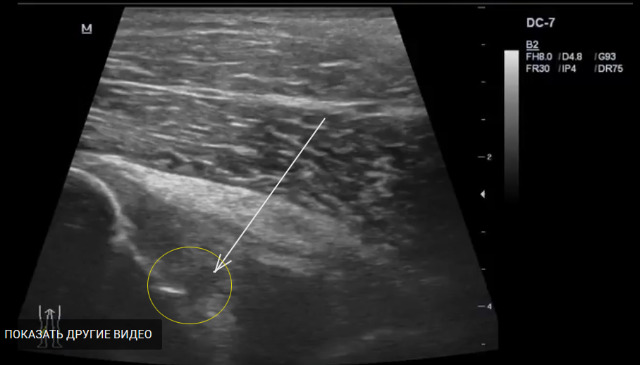

Поддержу Алексея,я за частичный разрыв.С учетом факта травмы я бы расценил как частичный разрыв (ЗКС).

Да и гадать здесь нечего, в данном случае частичный разрыв ЗКС и ПКС в проксимальной части.

Из видео четко видно, что обе связки резко утолщены и имеются несколько участко частичного разрыва.

ЗКС: